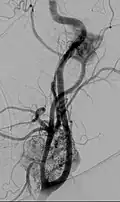

Digital subtraction arteriogram of carotid body tumor and jugular paraganglioma Digital subtraction arteriogram of carotid body tumor and jugular paraganglioma